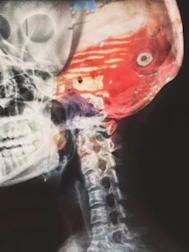

Tumori trattati in otorinolaringoiatria

Dott. Porro: l'otorinolaringoiatra è specialista di diagnosi e cura di tumori benigni e maligni di testa e collo

Il chirurgo dott. Giuseppe Porro, specialista in otorinolaringoiatria e chirurgia cervico-facciale, spiega che i tumori del distretto testa-collo di competenza dell'otorinolaringoiatra comprendono neoplasie che originano da diverse strutture anatomiche: cavo orale, gola (faringe e laringe), naso, seni paranasali e ghiandole salivari.

Il dott. Porro, specialista in otorinolaringoiatria e chirurgia cervico-facciale, spiega che circa il 90% dei tumori maligni nel distretto testa-collo è rappresentato dal carcinoma spinocellulare (o a cellule squamose), che origina dalle mucose. Tra i tumori maligni più frequenti ci sono i carcinomi della laringe (il sito più frequente), dell'orofaringe (tonsille, base lingua), della rinofaringe e dell'ipofaringe. Inoltre i carcinomi squamosi e adenocarcinomi dei seni etmoidali o mascellari, e poi i carcinomi di lingua, pavimento orale, gengive e labbra, o quelli alla tiroide (carcinomi papillari, follicolari e midollari) e ancora alle ghiandole salivari (carcinoma adenoidocistico, adenocarcinoma e carcinoma mucoepidermoide).